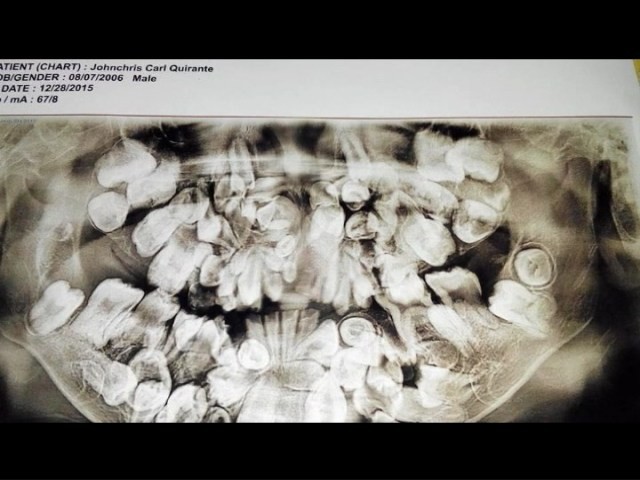

Do điều kiện kinh tế nên bố mẹ Johncris không đưa cậu bé tới gặp nha sĩ. Nhưng tới khi cậu bé 5 tuổi thì số lượng răng đã lên tới 150 chiếc, lúc này Johncris mới được đi chụp X-quang lần đầu tiên. Trong vòng 4 năm tiếp theo, tình trạng tồi tệ hơn khi 300 chiếc răng mọc chen chúc trong miệng cậu bé.

Khoảng 300 chiếc răng mọc chen chúc trong miệng cậu bé.